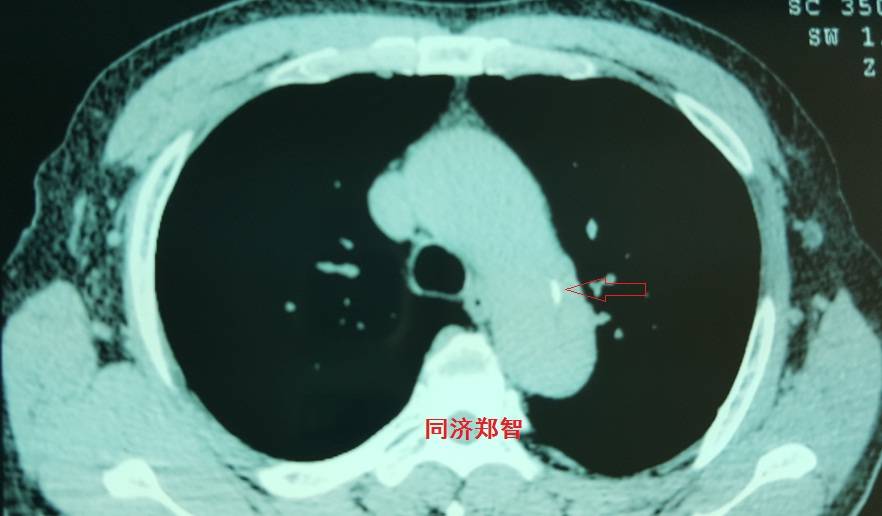

平扫CT提示主动脉弓层面及右肺动脉层面均可见主动脉血管腔内的内膜片影(红色箭头所示),CTA显示为A型主动脉夹层。